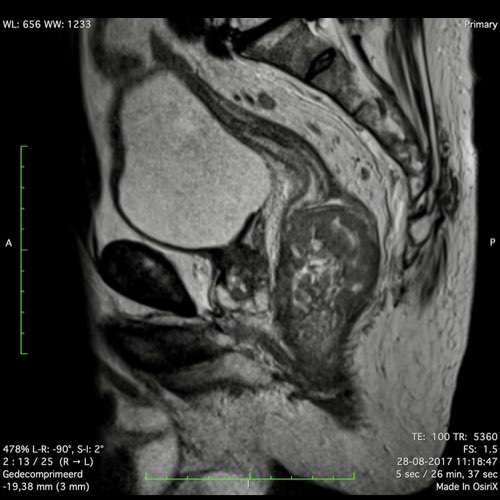

Hình ảnh

Các hình ảnh được cung cấp cho thấy ung thư biểu mô tế bào nhẫn với tình trạng dày lan tỏa thành trực tràng, hình ảnh bia bắn điển hình, và sự xâm lấn mỡ mạc treo trực tràng.